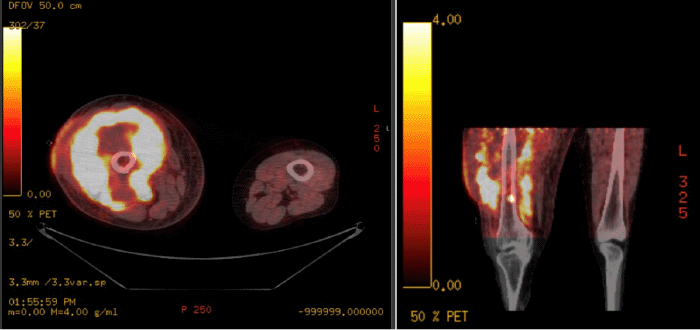

In the postoperative period, a comprehensive review of systems, facilitated by a licensed Spanish interpreter, revealed headaches, weight loss, and night sweats. MRI of the right thigh demonstrated a large, infiltrative mass originating from the right femoral shaft and extending into the anterior and posterior thigh compartments (Figure 2). Right inguinal adenopathy, small bony lesions of the femoral neck and posterior acetabulum, and abnormal marrow signal throughout the right femoral shaft were also noted. Staging CT and PET scans revealed a large heterogeneous mass in the right thigh, extending into the distal femur and knee joint, with bulky lymphadenopathy and heterogeneous mixed lytic and sclerotic changes of the right humerus, exhibiting intense fluorodeoxyglucose (FDG) uptake (Figure 3).

Figure 3. PET-CT Imaging for Lymphoma Staging. Published with Permission

Axial and coronal PET-CT images of the bilateral thighs demonstrating an intensely fluorodeoxyglucose (FDG)-avid mass in the right thigh, extending into the distal femur and knee joint